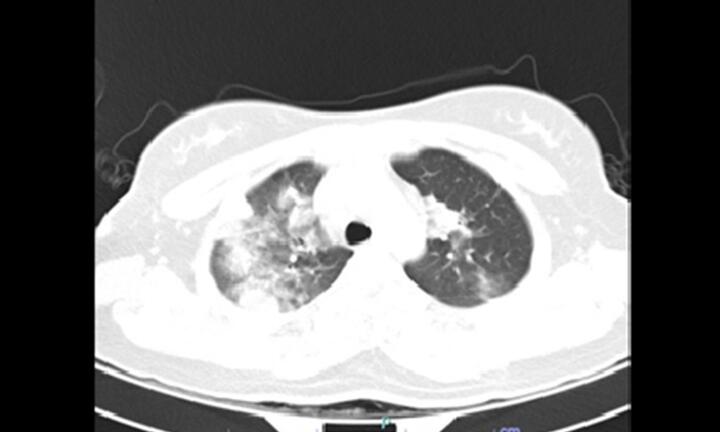

Sau khi khỏi COVID-19 một tháng, nữ bệnh nhân có biểu hiện ho đờm, sốt cao 39 độ C, đau tức ngực 2 bên, khó thở tăng dần trong 3 ngày.